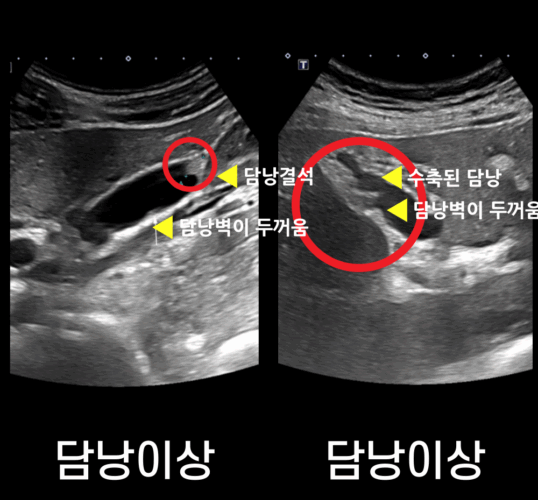

– 담낭·담도·간·신장 등 1차 평가에 유용